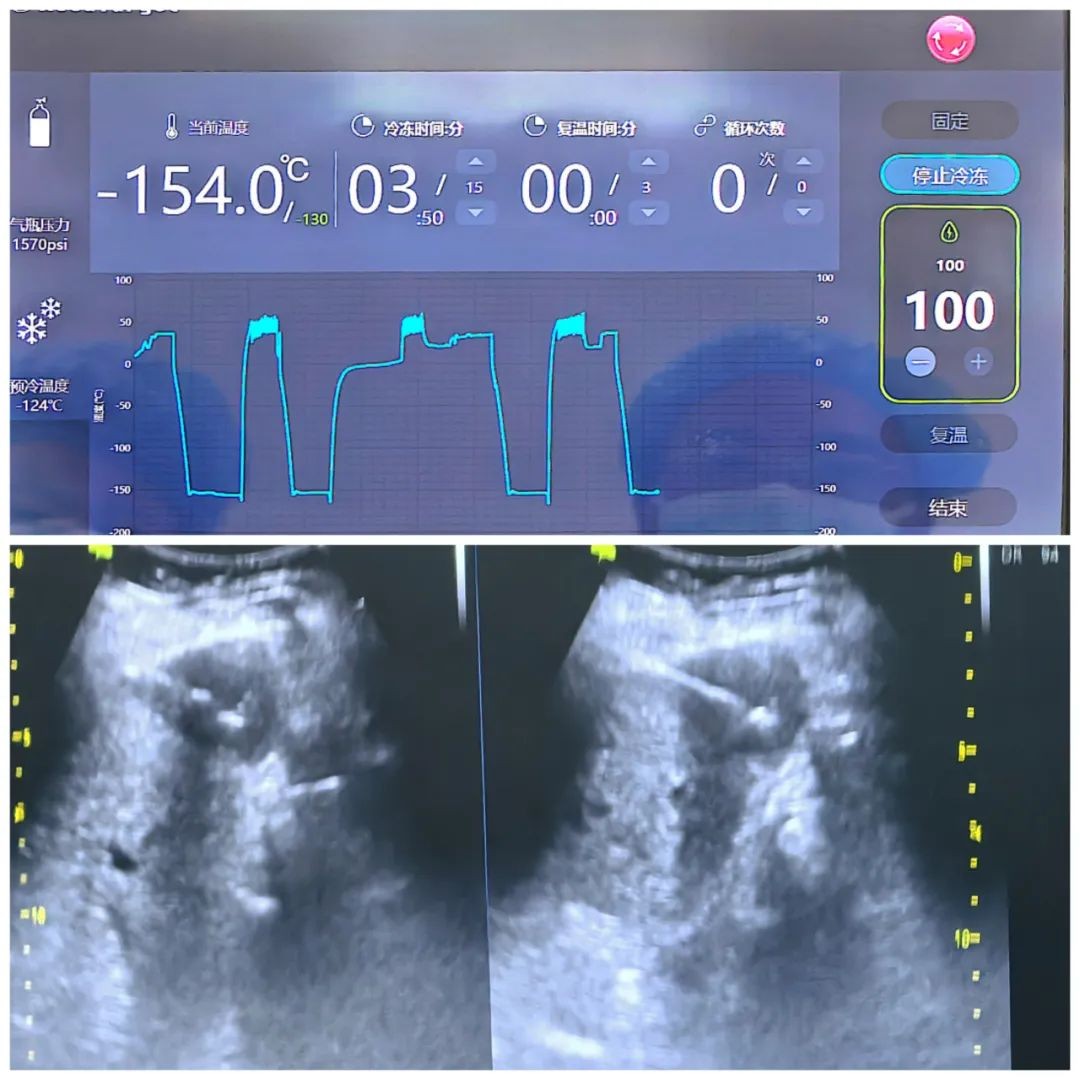

一个月后,患者再次入院,CT检查病灶内碘化油沉积充分,体积缩小,AFP降至正常水平。微创介入中心专家团队按计划为颜先生行超低温冷冻消融治疗,由于病灶位于S6段,紧贴肝包膜,邻近结肠肝曲和右肾上极,超低温冷冻消融治疗可以最大程度保全邻近组织解剖结构,介入科龚明医生在全麻下超声引导精准穿刺病灶中心,开启冷冻至零下154℃,使冰球包裹病灶,经3次冷冻-复温循环,用时1小时结束手术,患者至ICU观察24小时后安返病房,四天后顺利出院。